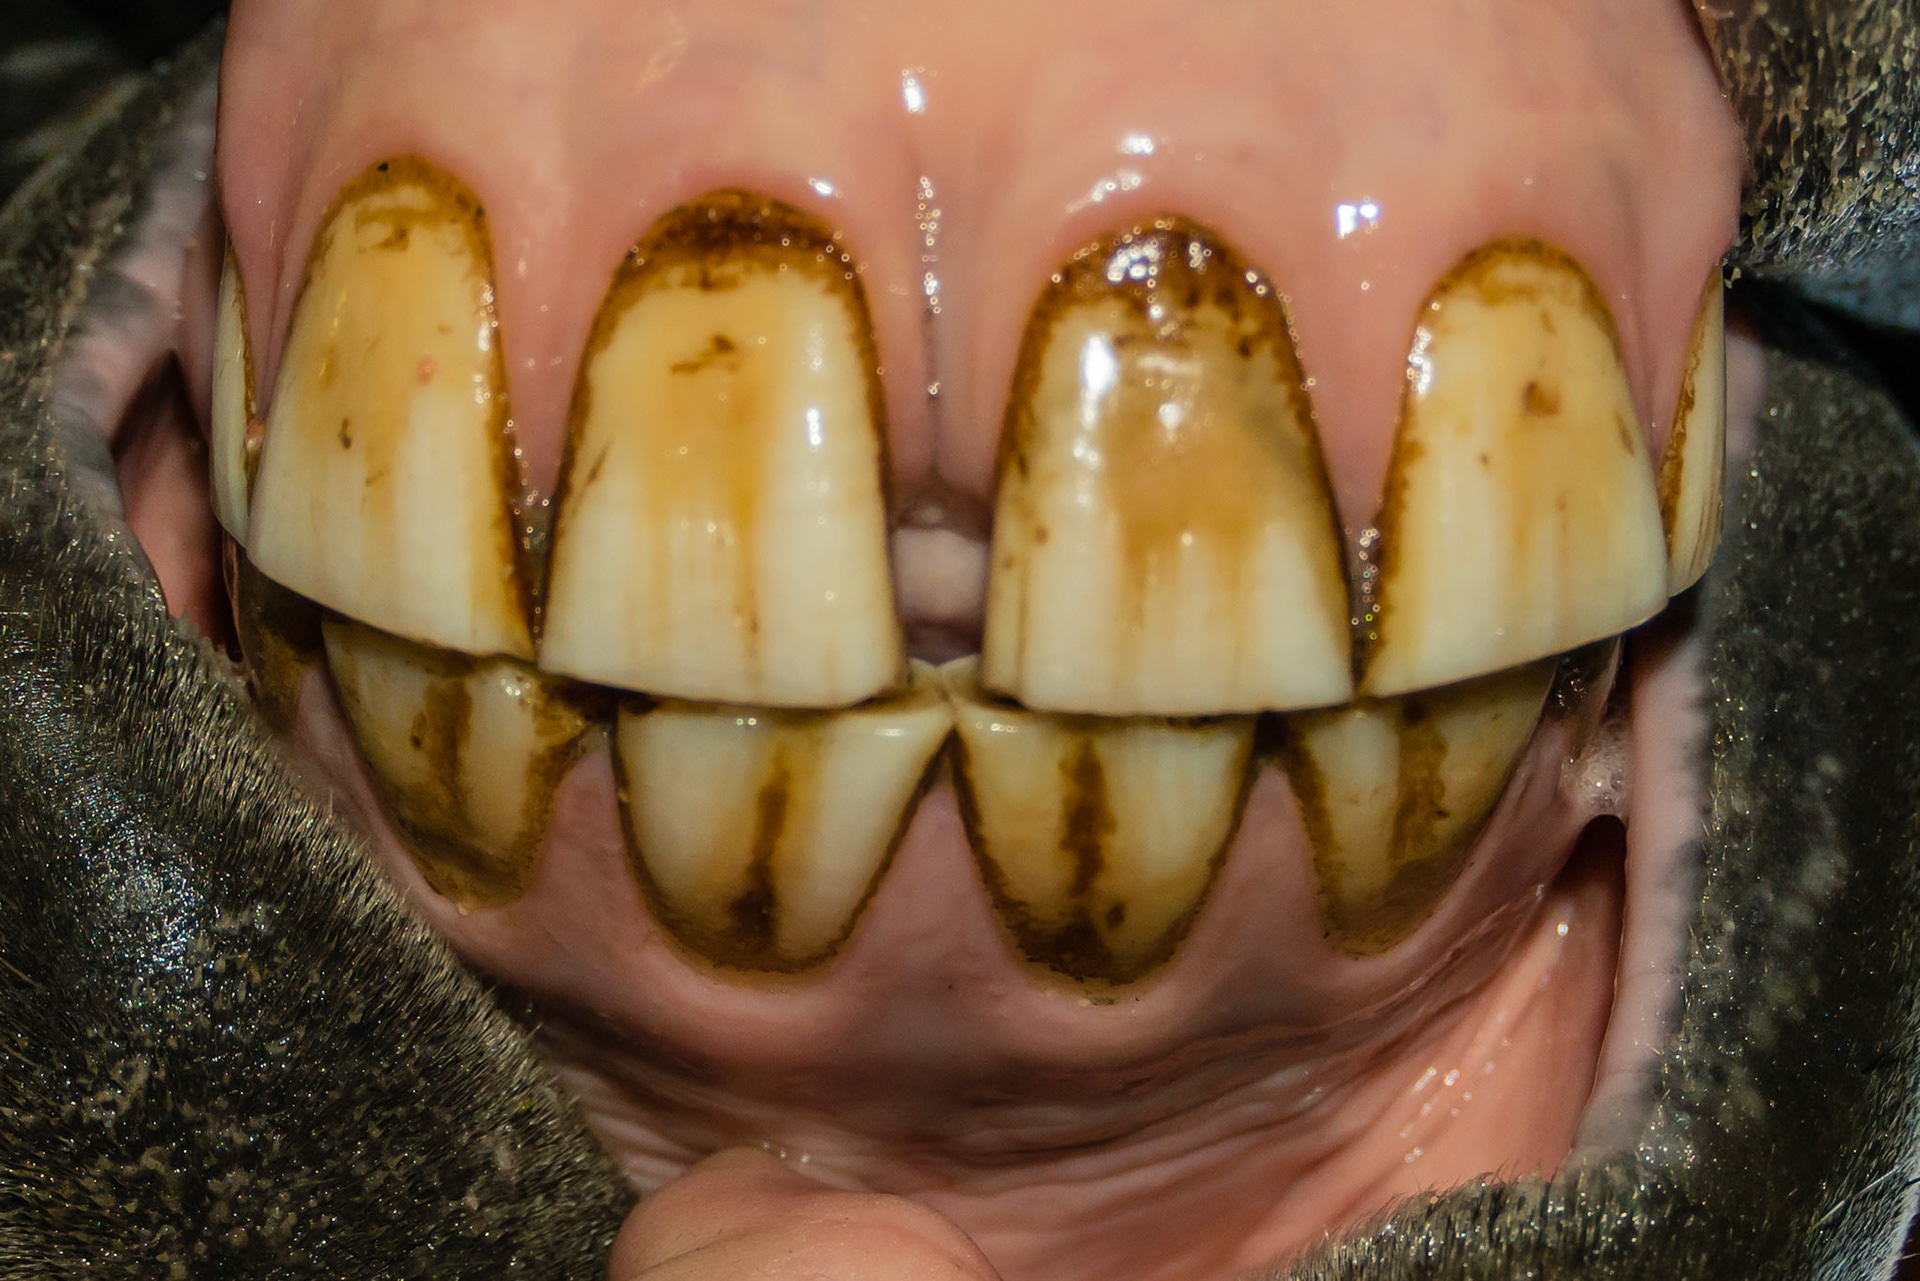

6yr old  Damaged and stained surfaces of all incisors.  Unknown history.